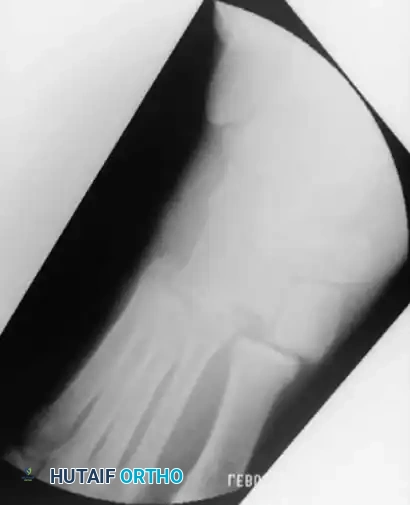

Radiographic Evaluation and Positioning

Accurate radiographic evaluation is paramount. Standard anteroposterior (AP), lateral, and mortise views of the ankle are required, but the Canale view is essential for evaluating the talar neck.

To obtain the Canale view, the foot is placed directly under the x-ray tube, and the ankle is placed in maximal equinus—the usual position after the reduction of a talar neck fracture. This position can be maintained more easily by maximal flexion of the hip and knee. The foot is pronated 15 degrees, and the x-ray tube is directed cephalad at a 75-degree angle from the horizontal tabletop. This specialized technique enables the surgeon to detect any subtle offset, comminution, or varus deformity of the head and neck of the talus.